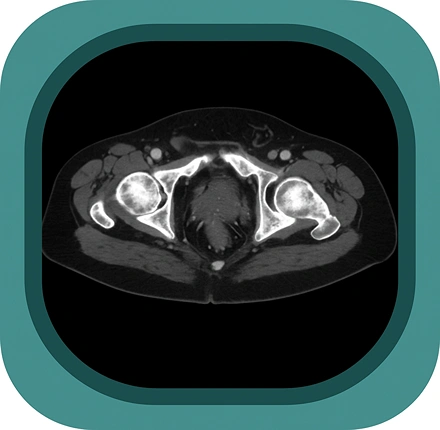

Explore full-body CT anatomy in 3 planes. Our high-resolution, carefully labelled images reveal micro-anatomy—ideal for radiologists, radiographers and surgeons.